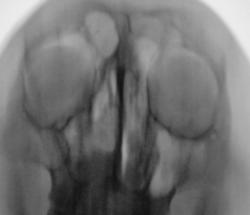

Ваше мнение коллеги по представленным снимкам и томограммам. Каждая иллюстрация представлена в двух вариантах - без обработки изображения и с "обработкой".

Да. Перевернуты только томограммы, на которых левая сторона слева, а правая - справа. В анамнезе была операция, какая, пациент уточнить не может. В настоящее время  появились боли распирающего характера слева, чувство заложенности, направлен на исследование "без диагноза".